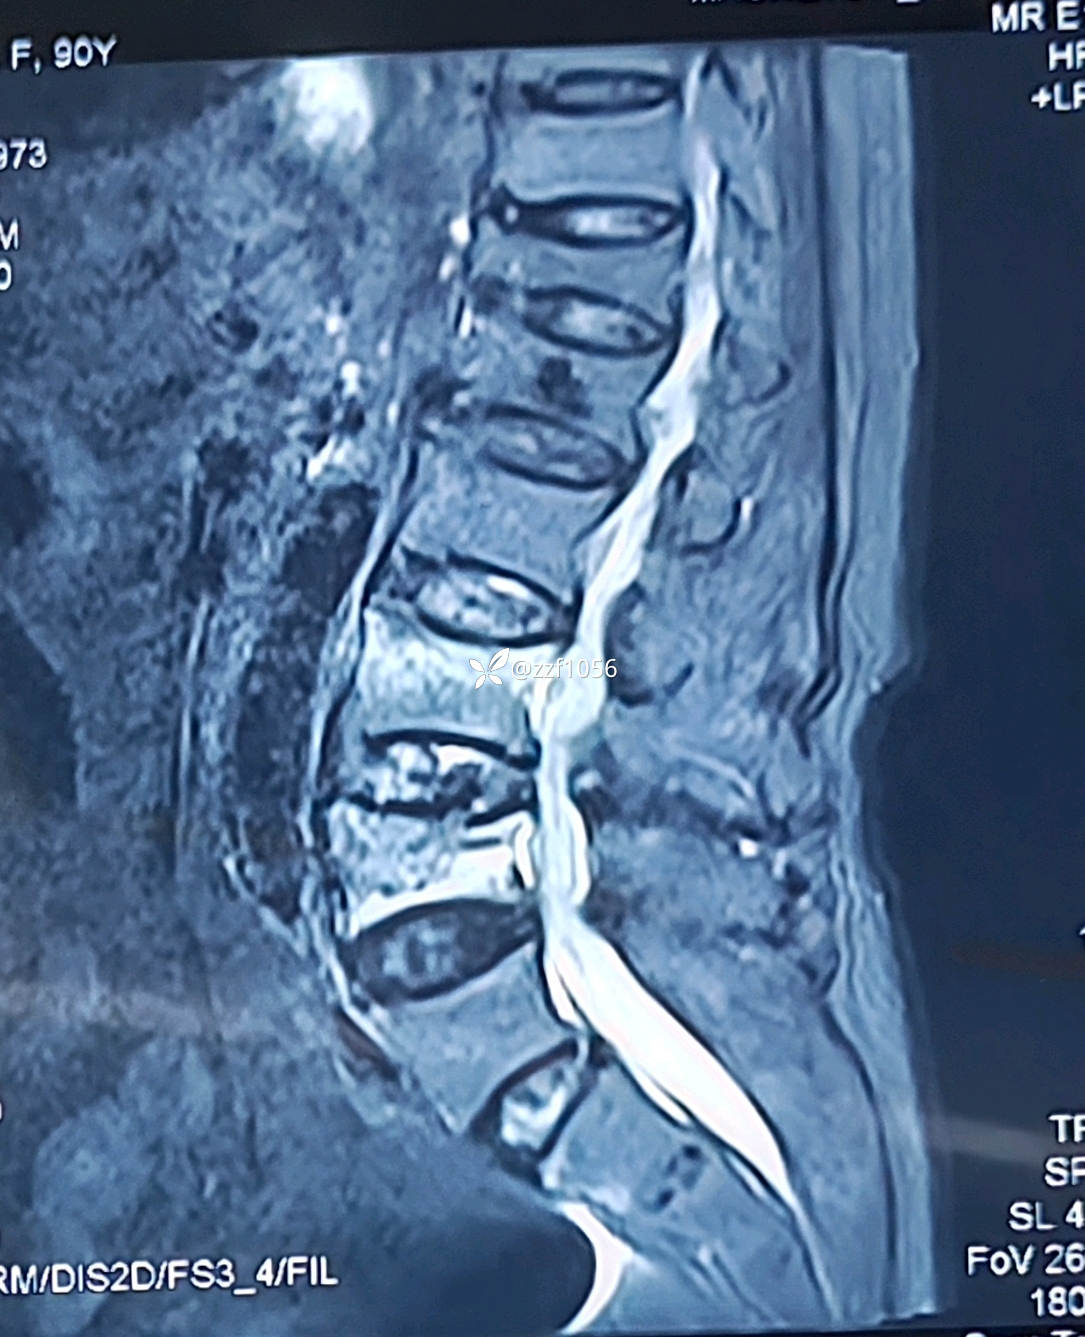

腰3腰4椎体压缩性骨折明确

果不其然,骨水泥渗漏入椎管内,非常能感受到当时主刀惊出一身汗😓,万幸的是患者并没有神经症状。

家属自诉一年前患者腰1压缩骨折,在外省地医院行椎体成形术,术后恢复良好,日常正常行走。